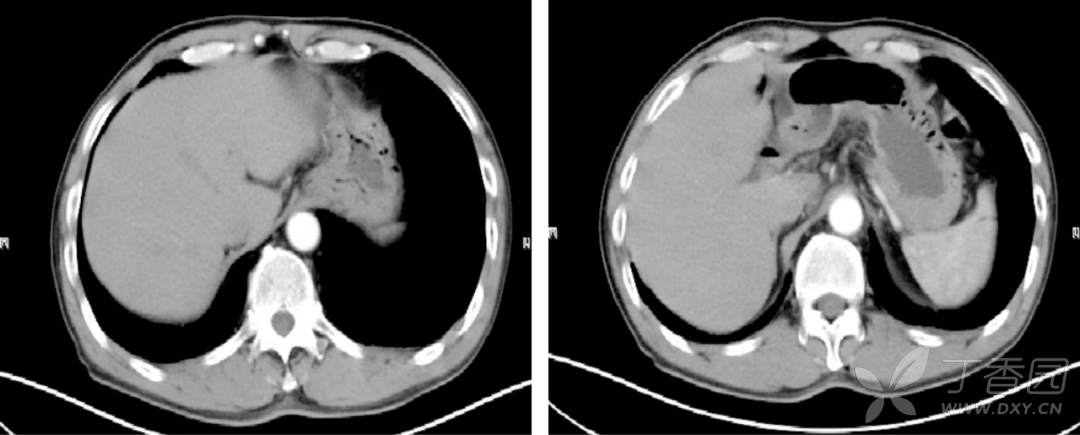

肝脏 CT: